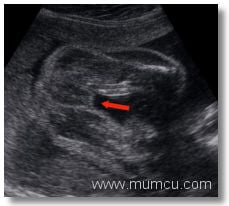

Kiz bebek